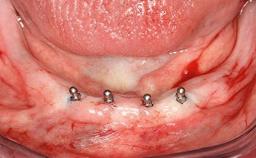

An 83-year-old man presented together with his caregiver at the dental department of the Medical University of Innsbruck, Austria with complaints of swelling in the right maxillary canine area and loss of retention of his 5-years-old mandibular denture. The patient had a significant medical history (20 years) of bipolar affective disorder with moderate depression (F 31.3) and dementia in Alzheimer’s disease (F 00.2). The patient had been in ambulant psychiatric therapy for his depressive illness for the past 20 years. He lived alone and had no children; his sister assisted with daily living. She reported that the patient exhibited compulsive hoarding behavior. In the previous two months, she had noted increasing disorientation and vertigo in the patient. She therefore accompanied him for a medical consultation at the Department of Psychiatry and Psychotherapy of the Medical University of Innsbruck. He was released home after a 6-week inpatient stay.

# of Implants 2

Type of Implants One-Piece

Attachment One-Piece

Defining Characteristics Fully edentulous lower jaw to be rehabilitated with two or more implants

Modality 2 interforaminal implants